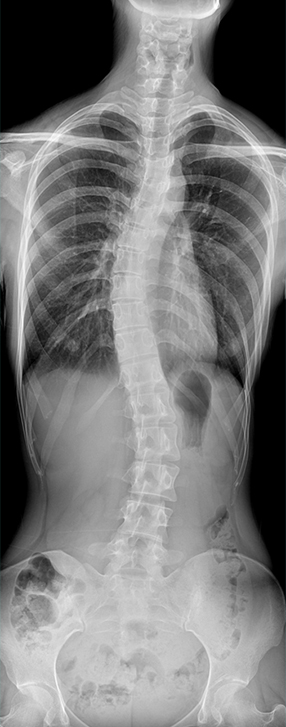

• 拍片

适用于全身各部位摄影

(常规摄影和特殊摄影)